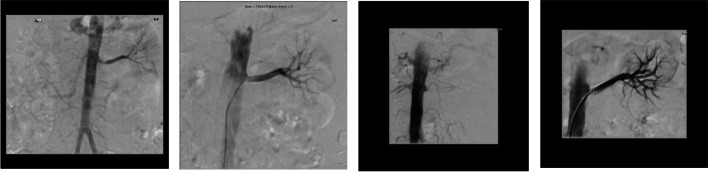

Fig. 2.

(from left to right). 1) L RAS presenting as severe hypertension. 2) Successful L PTRAS with BP on target with single agent. 3) 5 years later LRAS presenting as anuric AKI. 4) Successful L PTRAS with immediate urinary output. (Patient 5)

| 5 | 63 yr male transferred for AKI on CKD |

CKD 3 (ARVD within previous L PTRAS in 2012) HTN Previous ischaemic stroke NIDDM Hyperthyroidism treated with radioactive iodine therapy Smoker |

BP: 198/92 mmHg on 3 agents Creatinine: 319 µmol/L(eGFR: 9 ml/min) uPCR: 800 mg/mol |

Formal Angiogram: Occluded L stent |

L PTRAS (Fig. 2) |

Within 1 month: BP: < 130/80 mmHg on no agents Creatinine:240 µmol/L (eGFR: 24 ml/min) uPCR: 132 mg/mol |